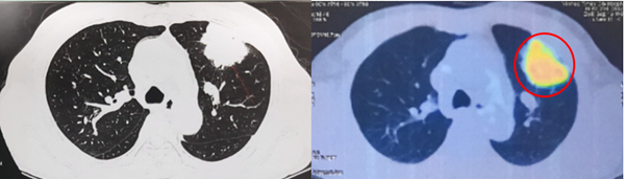

- Cắt lớp vi tính lồng ngực có tiêm thuốc cản quang:

Hình 1. Khối u kích thước 51x58x42mm thùy trên phổi trái, ngấm thuốc không đều sau tiêm (vòng tròn đỏ).

PET/CT toàn thân với 18FDG:

Hình 6: Hình ảnh khối tăng chuyển hóa FDG ở thùy trên phổi trái tương ứng với tổn thương nguyên phát đã biết (vòng tròn đỏ) (cT3).

Hình 7: Chưa phát hiện hạch to, tăng chuyển hóa FDG khu trú bất thường ở trung thất - hố thượng đòn, rốn phổi 2 bên (cN0).